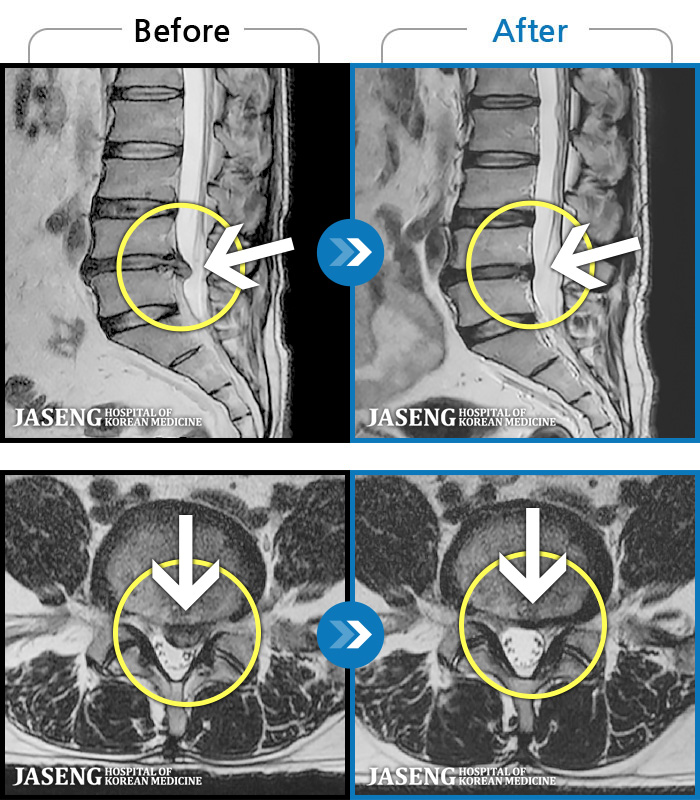

MRI 치료사례

내원 당시 추간판 탈출증으로 인한 요 골반통과 좌측 하지 방사 통으로 보행 및 일생 상활이 어려웠습니다.